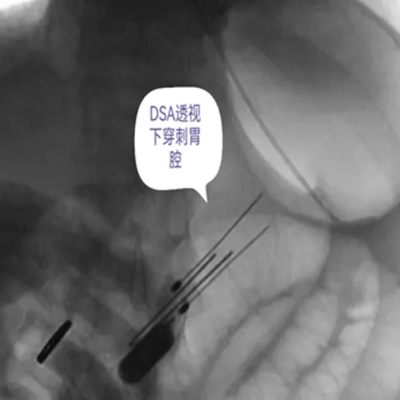

DSA引导下经皮胃造瘘术,是在数字减影血管造影(DSA)这个“透视眼”的实时可视化导航下,于患者腹壁上建立一个仅 3-5毫米 的微小穿刺点。通过这个“针眼”,医生精准地将一根营养管直接置入胃部,建立起一条直达的营养通道。

整个过程就像一次精准的“导航穿刺”,全程操作便捷、创伤小,却能完美替代传统的鼻饲管,为患者提供长期、稳定、安全的营养支持。

医院临床实践中就有典型案例:一名65岁食道癌伴淋巴结转移患者,因食道狭窄无法插入胃镜,且体质虚弱难以耐受全麻手术,团队借助DSA精准导航,仅用10分钟便完成手术,局部麻醉下患者全程无明显不适,术后1天即可通过造瘘管补充营养,为后续抗肿瘤治疗顺利开展奠定了坚实基础。